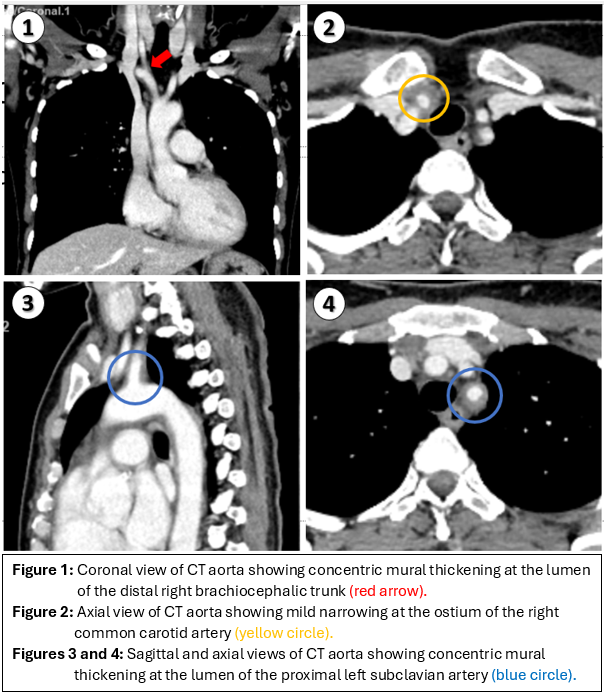

Initial investigations showed favorable lipid profile (LDL51 mg/dl) and HbA1C level of 4.9%. Considering the presence of isolated aorto-ostial disease leading to acute left main STEMI, further investigations were conducted to assess for aortitis, including ankle-brachial index and serology for antinuclear antibody (ANA), antineutrophil cytoplasmic antibody (ANCA), rheumatoid factor, syphilis, and HIV, all of which were negative. However, the patient demonstrated elevated levels of erythrocyte sedimentation rate (ESR) and C-reactive protein (CRP), indicative of systemic inflammation. A computed tomography angiography (CTA) of the whole aorta revealed concentric mural thickening in the lumen of the distal right brachiocephalic trunk, proximal right common carotid artery, proximal right subclavian artery, and proximal left subclavian artery with mild narrowing at the ostium of the right common carotid artery. These findings were suggestive of Takayasu arteritis type I.